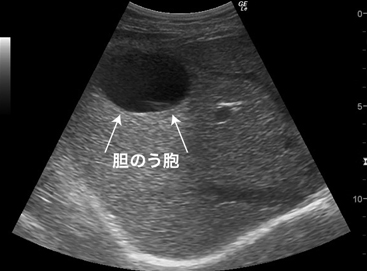

Bile Cyst

直径30mm的局部化低亮度

It was seen as a low-luminance, localized region with a diameter of 30mm